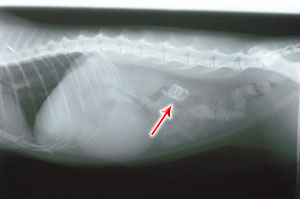

Roxy's X-Ray

Some cats will eat anything they can get down their throat. Most of the time, it's harmless items that get digested, or are small enough to go through the digestive system without harming the animal, but on rare occasions we do see strange X-Rays like ROXY's who had ingested 4 pennies (not the best way to save!).